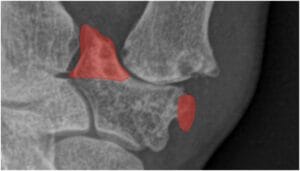

Removal of the medial and lateral osteophytes at the distal articular surface of the trapezium.

Resection of the volar beak at the base of the thumb metacarpal.

The cup’s placement in the trapezium parallel with the proximal articular surface of the trapezium aligns it with the centre of motion of the normal thumb carpometacarpal joint.